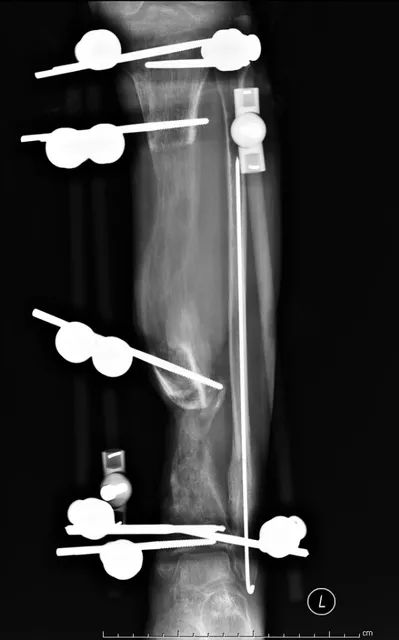

(网友提供)最后的病例是伤后40天由外地转来。开放骨折外固定架固定,骨坏死外露,用连珠和双氧水冲洗。入院时还存在足下垂,腓神经损伤、胫后动脉损伤。

Tips

• 接收该患者后第一次手术  清除病灶去除死骨27cm

• 抗生素骨水泥填塞。远端整块水泥包裹外露骨质,近端连珠以便骨搬移

• 钢丝克氏针张力牵拉皮肤,缩小创面

• 5天后下地部分负重走路

• 联合骨牵引纠正足下垂,5天后足下垂纠正后去除跟骨骨牵引针,保留胫跖骨牵引维持足于功能位。

• 而后行骨搬移、半开放植骨(如下)

• 第一次的骨水泥于80天后去除,行半开放植骨(植骨表面覆盖抗生素骨水泥)

• 因为有皮肤缺损,用骨水泥做成瓦片闭合伤口=半开放植骨

• 自体优质松质骨(如图)

• 皮肤采用了钢丝牵张闭合

• 骨搬移+半开放植骨=治疗缺损

• 植骨后一个月去除瓦片骨水泥,创面新鲜

• 钢丝克氏针张力闭合伤口加游离植皮

• 继续骨搬移

• 修整

• 入院6个月腓总神经恢复,胫前动脉再通

• 总的治疗过程2年基本完全康复